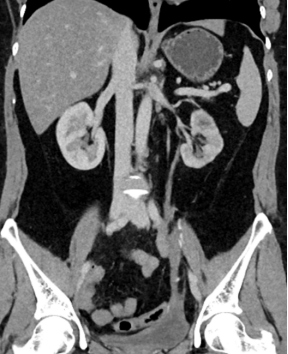

李女士术前CT

术后半年复查积水缓解(憋尿状态)